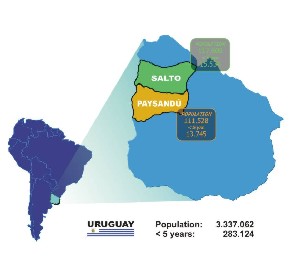

Realizar un estudio prospectivo de base poblacional en Paysandú y Salto, que capte todos los pacientes hospitalizados con infecciones respiratorias agudas documentadas por una radiografía de tórax con la finalidad de establecer la carga de esa patología y su potencial prevención con vacunación.

Sse llevó a cabo tres años de vigilancia en cuatro hospitales de ambos departamentos cubriendo 229.128 habitantes, de los cuales 10,2% son menores de 5 años. A cada paciente hospitalizado se le realizó una historia clínica padronizada y se obtuvo una fotografía digital de la radiografía de tórax. Un pediatra y un radiólogo pediatra, con prescindencia de la historia clínica, interpretaron las imágenes digitales que a su vez fueron evaluadas por una comisión internacional de expertos. La etiología bacteriana y viral fue investigada.